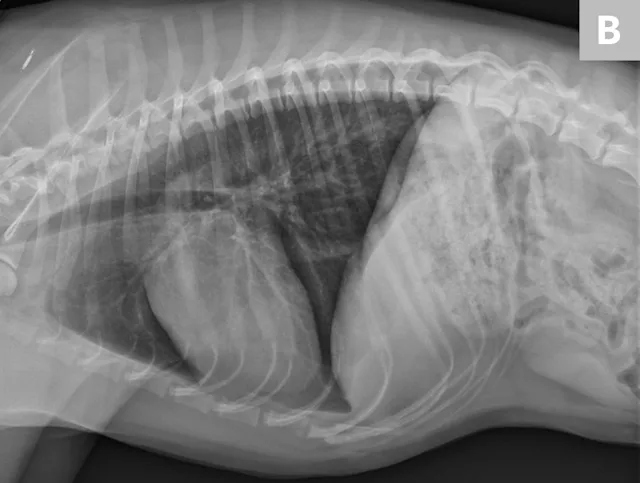

• Use the humanoid projection to visualize the cranial lung field and remove any superimposition of the caudal scapula. Place the patient in dorsal recumbency with the thoracic limbs pulled caudally along his or her side. The landmarks are the same as other views. (See Figures 7A & 7B.)

Figure 7A

Humanoid positioning with legs pulled caudally alongside the patient (A). Resulting humanoid view (B). Note the scapula are not superimposed over the chest.